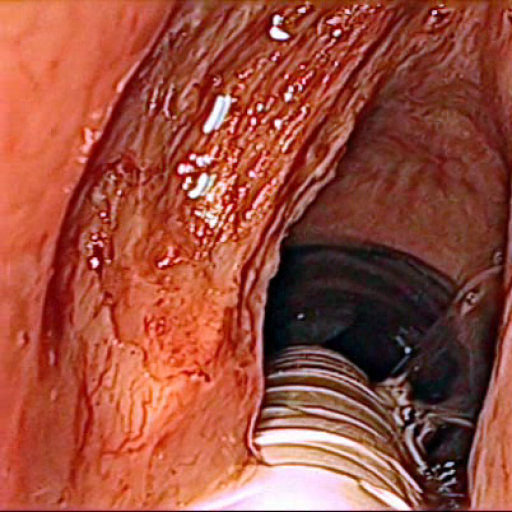

Figure 4 visualizes class label predictions for selected example images from the test set after training on the augmented dataset. As expected from the IoU values, the prediction of SegNet has major errors in classes pathology, vocal folds and other tissue. The results of UNet are better in general, but it provided visible errors on the edges of two adjacent areas. ENet and ErfNet both achieved good results, with ErfNet also resolving edges and smaller areas well. When zooming into the label maps, it is visible that ENet has a strong aliasing effect on the edges, whereas ErfNet results in smoother edges. The ensemble results are reported for ErfNet+UNet configuration, which provided overall best results. Please see the supplemental video material associated with this publication.

The prediction uncertainties in Fig. 4 give an estimate on how confident the model is for a specific pixel of the selected images. UNet and SegNet use normal dropout for stochastic inference, whereas ENet and ErfNet use spatial dropout (turning off full feature maps). In contrast to normal dropout, there is currently no proof of spatial dropout acting as Bayesian approximation gal2016 . This must be taken into account when considering the uncertainty maps. It is worth mentioning that ENet and ErfNet have a higher uncertainty in general and especially on other tissue. A possible explanation for this could be the low numbers of parameters having less redundancies compared to UNet and SegNet (see Tab. 2). Furthermore, it can be observed that with the exception of ErfNet, all models show a high uncertainty for pathology. On the other hand, all models show low uncertainties for vocal folds, which can be interpreted as good generalization for this class.